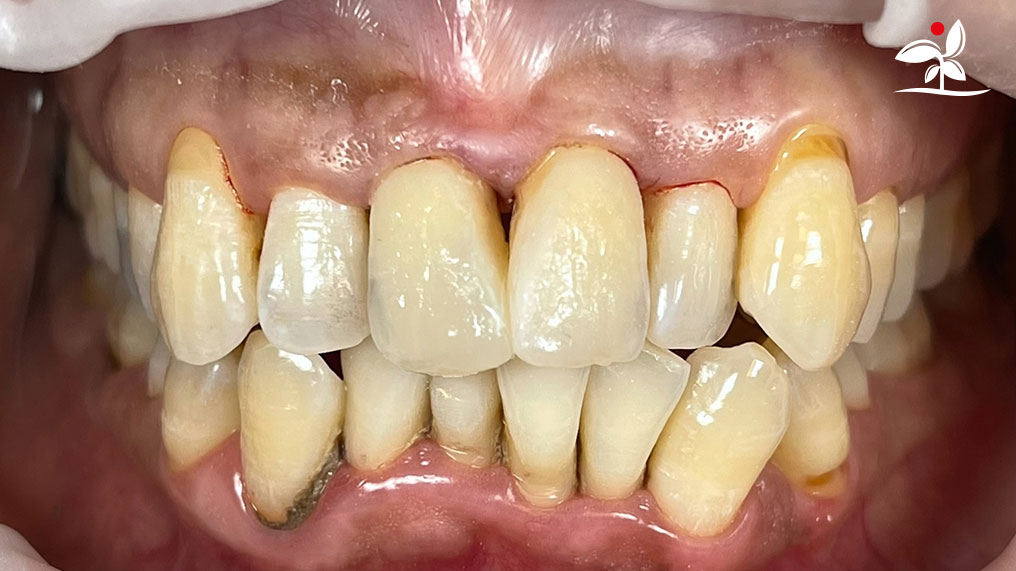

Restoration of Class IV Lesions using Naturomimetic Layering Technique (NLT) and Bioactive Restorative Materials

With the growing awareness about the health, function and aesthetic benefits of preserving natural tooth structure, patients are now globally demanding for aesthetic dentistry with minimally invasive procedures that has a low biological cost. This public demand has encouraged logical clinicians to adopt to the minimally invasive cosmetic dentistry (MiCD) concept and its treatment protocol [1] in their practice. The author has been using MiCD concept and its treatment protocols since 2017, which

include the methods of treatment that are simple, fast, predictable and healthy. In aesthetic restoration, the tooth color restorative materials placement technique is one of the most challenging, confusing and frustrating areas to learn owing to the multiple techniques that have been proposed by many clinicians and replicating such techniques in practice is not always as easy as they are marketed in dentistry. Natural teeth are complex in structure and hard to simulate due distribution of colors through enamel and dentin [2]. Aesthetic restoration strategies should follow proper understanding of defects, right selection of restorative materials along with their proper application, finishing, texturing and polishing [2].